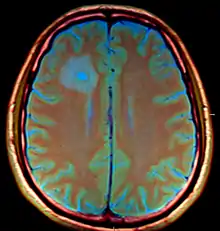

MRI (T1 with contrast) showing the ring-enhancing lesion. From a rare case report of an abscess formed as a complication of the CSF shunt. Jamjoom et al., 2009.[1]

The diagnosis is established by a computed tomography (CT) (with contrast) examination. At the initial phase of the inflammation (which is referred to as cerebritis), the immature lesion does not have a capsule and it may be difficult to distinguish it from other space-occupying lesions or infarcts of the brain. Within 4–5 days the inflammation and the concomitant dead brain tissue are surrounded with a capsule, which gives the lesion the famous ring-enhancing lesion appearance on CT examination with contrast (since intravenously applied contrast material can not pass through the capsule, it is collected around the lesion and looks as a ring surrounding the relatively dark lesion). Lumbar puncture procedure, which is performed in many infectious disorders of the central nervous system is contraindicated in this condition (as it is in all space-occupying lesions of the brain) because removing a certain portion of the cerebrospinal fluid may alter the concrete intracranial pressure balances and causes the brain tissue to move across structures within the skull (brain herniation).

Ring enhancement may also be observed in cerebral hemorrhages (bleeding) and some brain tumors. However, in the presence of the rapidly progressive course with fever, focal neurologic findings (hemiparesis, aphasia etc.) and signs of increased intracranial pressure, the most likely diagnosis should be the brain abscess.